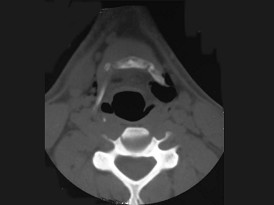

11.27岁男性,开车外出在高速行驶时翻车,呼吸困难,喉部肿胀,CT检查如图所示,请选择正确的描述或诊断 ( )![]() ![]() ![]() ![]() |

| 正确答案:ABCE |